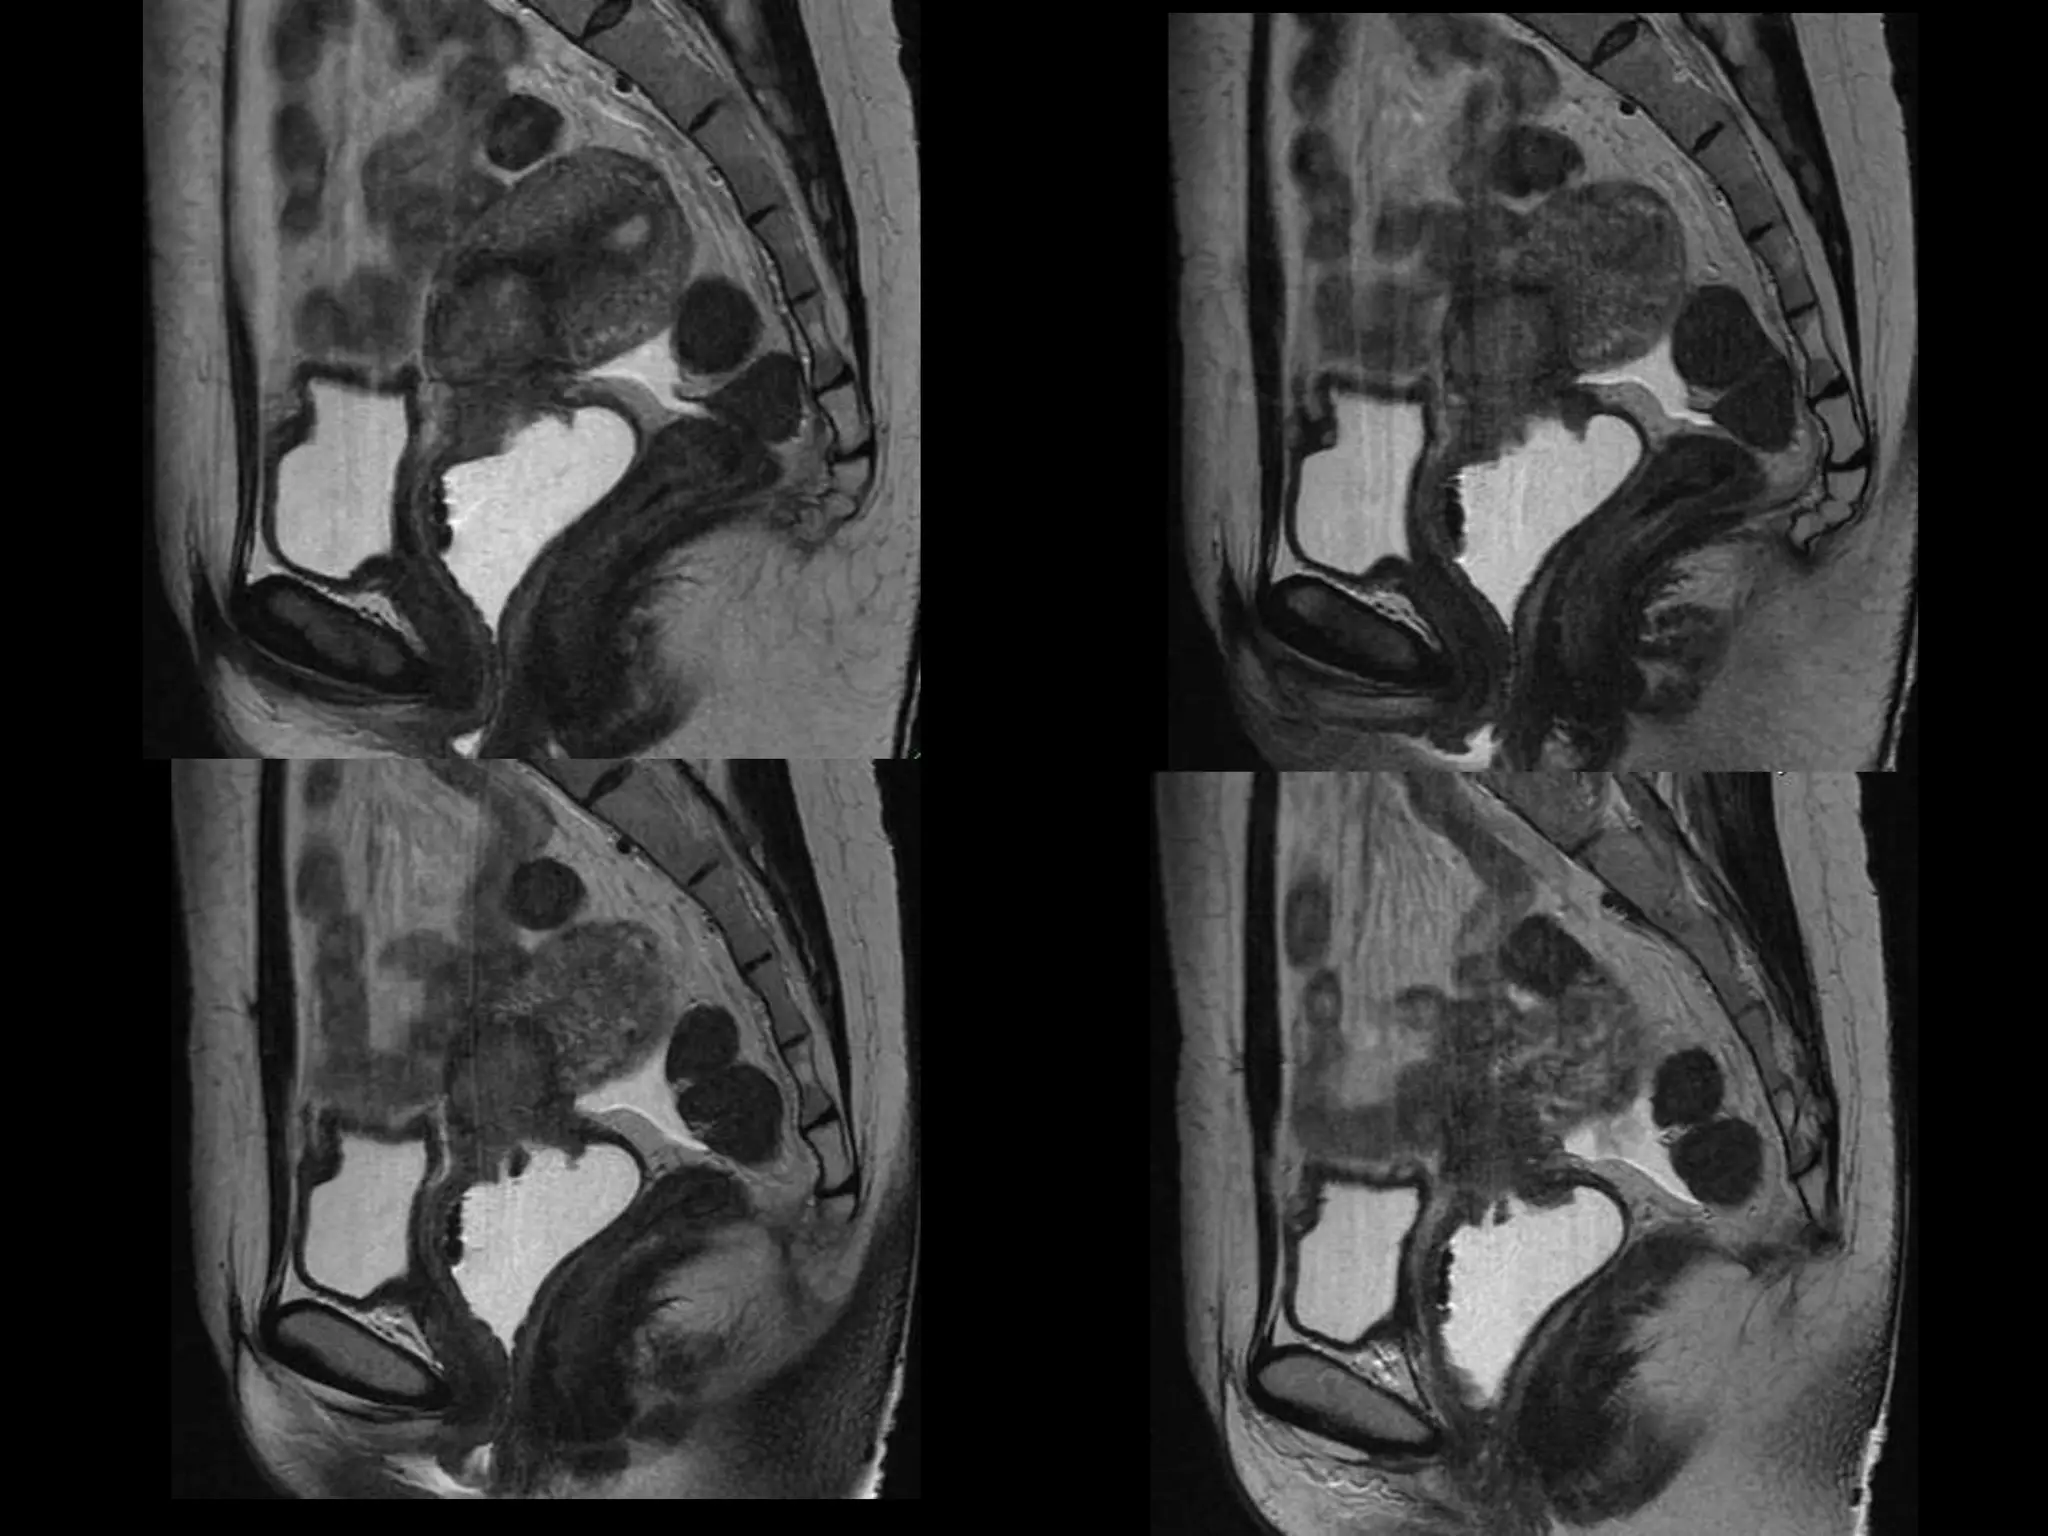

MRI findings - Stage IIB

with PET/CT - Stage IIIB

HISTORY โ€ข 42 yo female โ€ข Recent immigrant from China โ€ข C/O postcoital and intermenstrual bleeding โ€ข Abnormal GYN exam โ€ข Abnormal biopsy โ€ข Further imaging performed

MRI findings -Stage IIB with PET/CT - Stage IIIB Cervical Cancer

Stage I โ€“Carcinoma Confined to Cervix <= 4 cm greatest dimension > 4 cm greatest dimension <= 7 mm wide A1 < =3mm deep A2 >3 but < 5mm deep

Stage II โ€“Carcinoma Invades Beyond Uterus But not to Pelvic Wall or Lower 1/3 Vagina With(A) or without (B) parametrial invasion

Stage III โ€“Carcinoma to Pelvic Wall and/or Lower 1/3 of Vagina and/or Causes Hydronephrosis or Nonfxing Kidneys Lower 1/3 Vagina No pelvic wall Extends to pelvic wall and/or renal issues

Stage IV โ€“Carcinoma beyond True Pelvis or Involvement Of Mucosa of Bladder or Rectum (bx proven) Distant Mets Spread to adj organs

Role of MRImaging in Tx Stratification of GYN (Cervical) Cancer โ€ข Cervical Cancer โ€“ 2nd most common ca in women worldwide โ€“ Developing countries; pk 30-40 yrs โ€ข FIGO classification โ€“ revised in 2009 from just clinical to incorporate cross-sectional imaging (CT, MR) โ€ข Staging accuracy of MR 85-96% โ€“ Best test to assess tumor size and location; invasion into parametria, pelvic side wall, adjacent organs; local nodal enlgment โ€ข PET/CT helpful in staging advanced disease โ€“ Demonstrates unexpected sites beyond pelvis โ€ข Treatment options โ€“ Radical surgery - early stage (IA, IB1, IIA1) โ€“ Primary Chemo and Radiation โ€“ bulky IB2 or IIA2, or local advanced (IIB or greater) Sala et al. Radiology 2013; 266: 717.